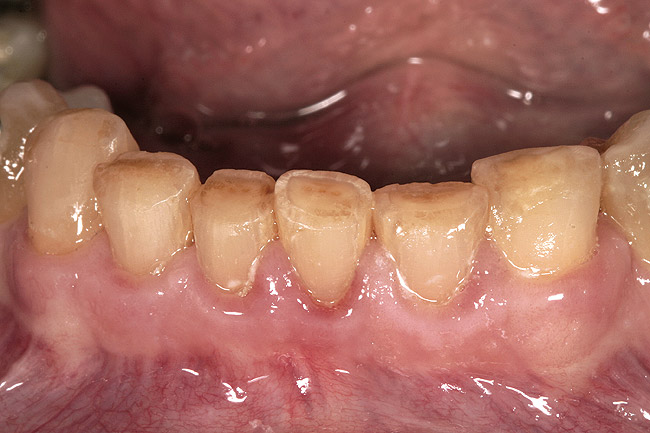

Figure 2  View of a patient with excessive wear and over-eruption of her incisors.

Figure 2